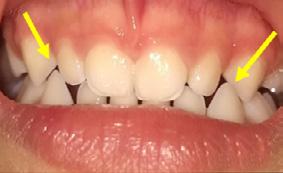

Paciente de 2años y 4 meses, femenino que fue presentada para valoración y consulta, primera dentición y sin caries, presentando hábito pernicioso de protrusión mandibular; normoclusión molar con mordida cruzada anterior (guía canina alterada) (Figura 5). La paciente presentó durante la valoración y consulta una conducta tipo I (- -) según la clasificación de la conducta Frankl y Wright. Mediante una cuidadosa valoración del caso, dada la situación habitual negativa, se diagnosticó como MCA funcional. El plan de tratamiento basado en la posibilidad de realizar un procedimiento práctico y adecuado fue el de realizar solo un ligero y cuidadoso desgaste de los puntos de contacto en la cúspide canina y distal de

.5 mm. En la cita subsecuente se observó el objetivo buscado mediante el asentamiento más ideal de la guía canina. La madre Figura 4. A) 72 horas posterior a la colocación. B) Primera activación. C) Segunda activación. D) Avance, tercera cita.

Figura 5. A) Posición de los caninos inferiores alterando la guía. B) Guía canina liberada tras el ajuste oclusal en ambas cúspides caninas inferiores. C) Protrución del labio. D) Retrución de labio una semana después.

reportó la eliminación gradual de la parafunción.